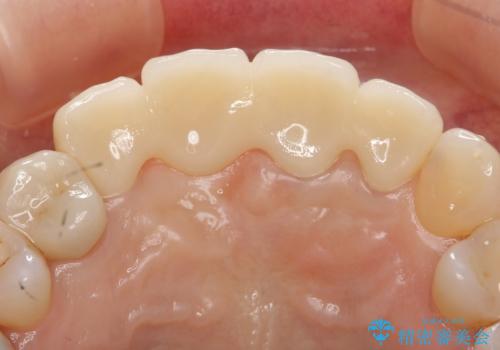

- 下顎前歯部の突き上げで上顎前歯の被せ物が土台ごと外れてしまった方の症例です。

右上1番目の歯は根元まで割れてしまっており、保存不可能だったため抜歯となりました。

抜歯後、骨と歯肉の回復を待ち、オールセラミッククラウンによるブリッジで補綴を行いました。

今回用いたオールセラミッククラウンはジルコニアフレームという白い素材の上にセラミックを盛っているため、審美性が非常に高いのが特徴です。

また、ジルコニアは人工ダイヤモンドの材料にも使われているほど高い強度を持っており、そのためオールセラミッククラウンは審美性だけでなく、奥歯やブリッジの補綴も可能とするクラウンです。